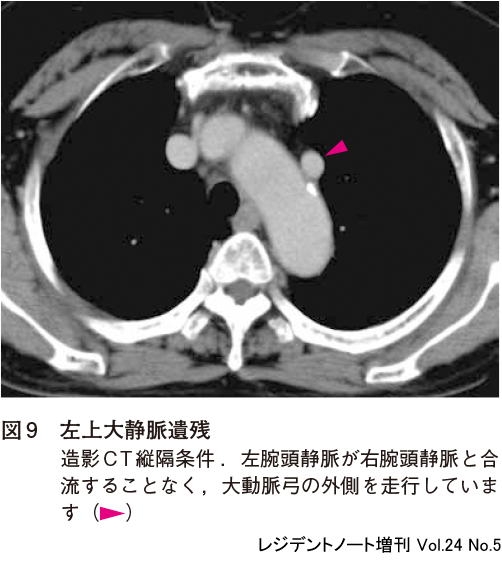

胸部CTを用いた肺ガン検診について | 市立秋田総合病院,胸部CTのおすすめ|日本赤十字社 熊本健康管理センター,レジデントノート増刊:読影力がグッと上がる!胸部X線写真・CTの読み方、考え方〜疾患別に読影の基本と各科での経過観察のポイント、撮影のタイミングがイチからわかる! - 羊土社,胸部CT2(縦隔条件),胸部CTの適応と基本的読影2: やさしイイ呼吸器教室